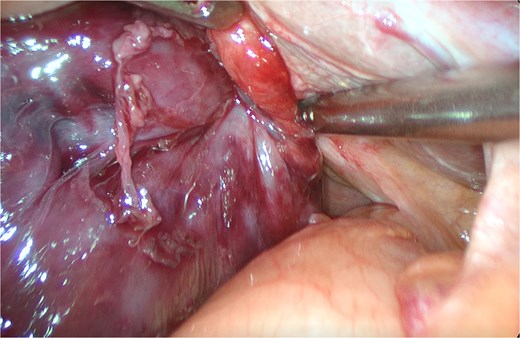

An 82-year-old female presented to the emergency department with a 2-day history of right upper quadrant pain accompanied by nausea and vomiting. The patient was hunched and thin, with a body mass index of 15.0 kg/m2 (Fig. 1). Physical examination revealed abdominal tenderness and a positive Murphy’s sign. Routine blood examination showed a white blood cell count of 16.5 × 10 [5], C-reactive protein of 3.83 mg/L, and normal liver function and electrolytes. A non-contrast abdominal computed tomography (CT) scan (Fig. 2) and gallbladder US (Fig. 3) were performed. We administered analgesics and antibiotics for 24 hours based on US and CT findings indicating impacted stones in the neck of the gallbladder. However, the patient’s symptoms of persistent abdominal pain did not improve, prompting us to proceed with laparoscopic exploration. During the operation, a necrotic gallbladder was identified within the confined space of the abdominal cavity (Fig. 3). Subsequently, intraoperative puncture decompression of the gallbladder was performed, followed by exploration via manipulation and rotation of the gallbladder using laparoscopic instruments (Fig. 4). The gallbladder was found to be completely mobile and had undergone a 360°clockwise torsion (Fig. 5). We successfully performed a laparoscopic cholecystectomy and pathological examination showed acute gangrenous cholecystitis. The patient was discharged on the fourth postoperative day.